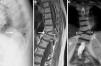

Radiografía lateral de columna dorsal mostrando un aparente aplastamiento vertebral cuneiforme anterior de D10 (A, flecha). La RM mostraba en los cortes sagitales de la secuencia potenciada en T1 un acuñamiento anterior similar al observado en la radiografía (B, flecha), pero en los cortes coronales se evidenció que en realidad correspondía a un defecto de fusión del cuerpo vertebral, que originaba la presencia de 2 hemivértebras, la derecha ligeramente menor que la izquierda, con la apariencia típica de «vértebra en mariposa» (C, cabezas de flechas).